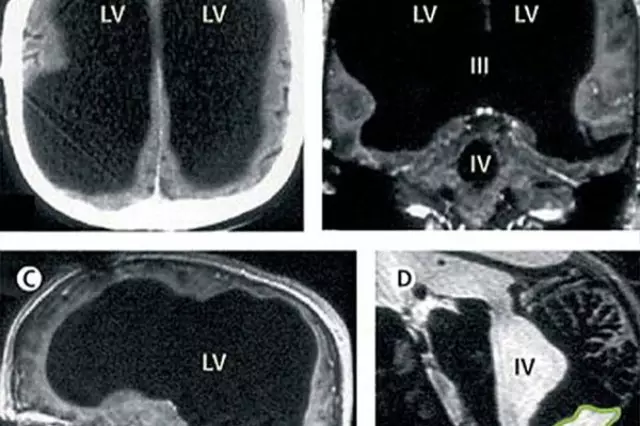

X光片显示,该男子75%的脑组织已消失不见

法国一名男子曾因腿部疼痛去医院检查,医生却找不出病根。在对其进行了全身体检后才发现,原来这名男子的腿疼是由脑部病变引起的,而该男子的大脑只剩下正常人大脑体积的一半都不到了。

这件事其实发生在2007年,近日由著名医学杂志《柳叶刀》披露。这名大脑神秘消失的男子当年44岁,医生在对其进行脑部检查后发现,他左右半脑上的额叶、顶叶、颞叶及枕叶都萎缩了。

在对这名男子的病史进行详细调查后发现,原来他童年时患有后天脑积水症。但在他14岁时,经历了分流术,随后的30年,这名男子和家人都以为完全康复了。但其实他的大脑还是在病变,最终,脑内的积水损坏了脑组织,导致其大脑50%至75%的部分都消失了。